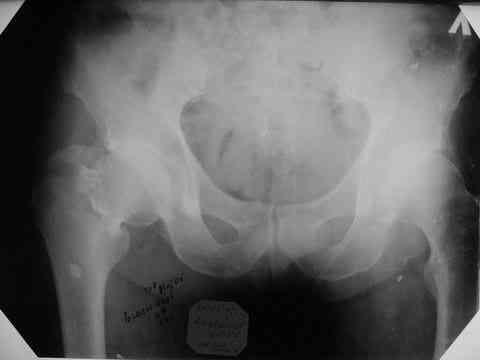

Все-таки хочу поделиться раз затронулась тема, может кому-нибудь и сгодиться. Это пример из области скорее трудноудаляемой. Пациент 50 лет, травма (низкоэнергетическая) 1,5 года назад. Оперирован через неделю (винт отечественный). Через 4 месяца выполнен контрольный снимок, сразу же возник вопрос: почему винт не телескопировался? Вопрос в общем-то так и остался без ответа.

При удалении (наркоз) после неимоверных усилий пришлось выкрутить фиксатор единым блоком и только тут все встало на свои места. См. фото.

Грустно+ Вот какие сюрпризы преподносят иногда коллеги.